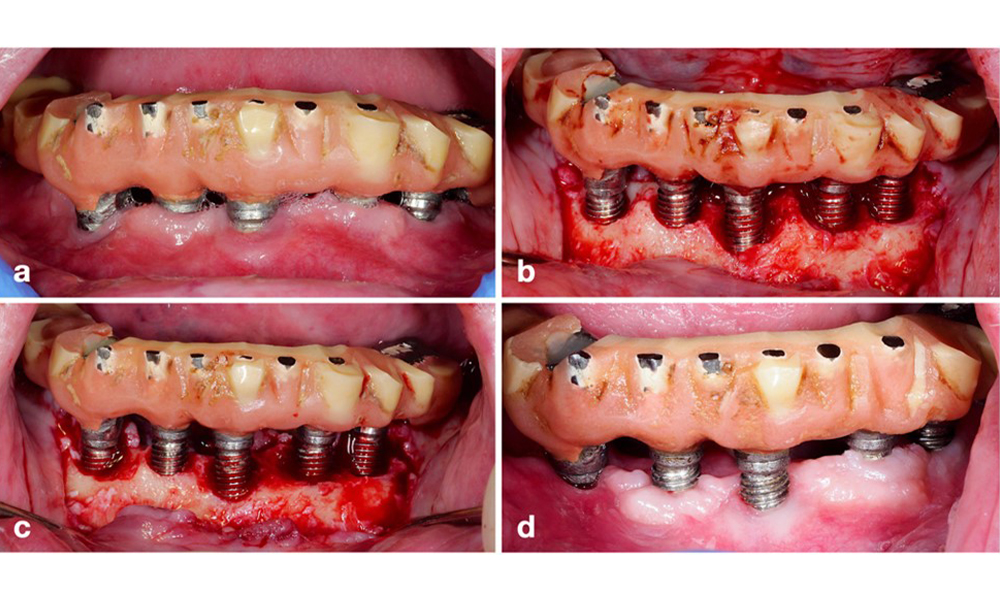

Defect extent, implant position, and its strategic importance determine whether an implant can or should be treated. Similar to a non-treatable (hopeless) implant, a severely affected implant in a multiple-unit restoration may be irrelevant for treatment, as its loss does not compromise the prosthetic restoration. Consequently, it is advisable to consider explantation either upon diagnosis or during surgical intervention (figure 8).